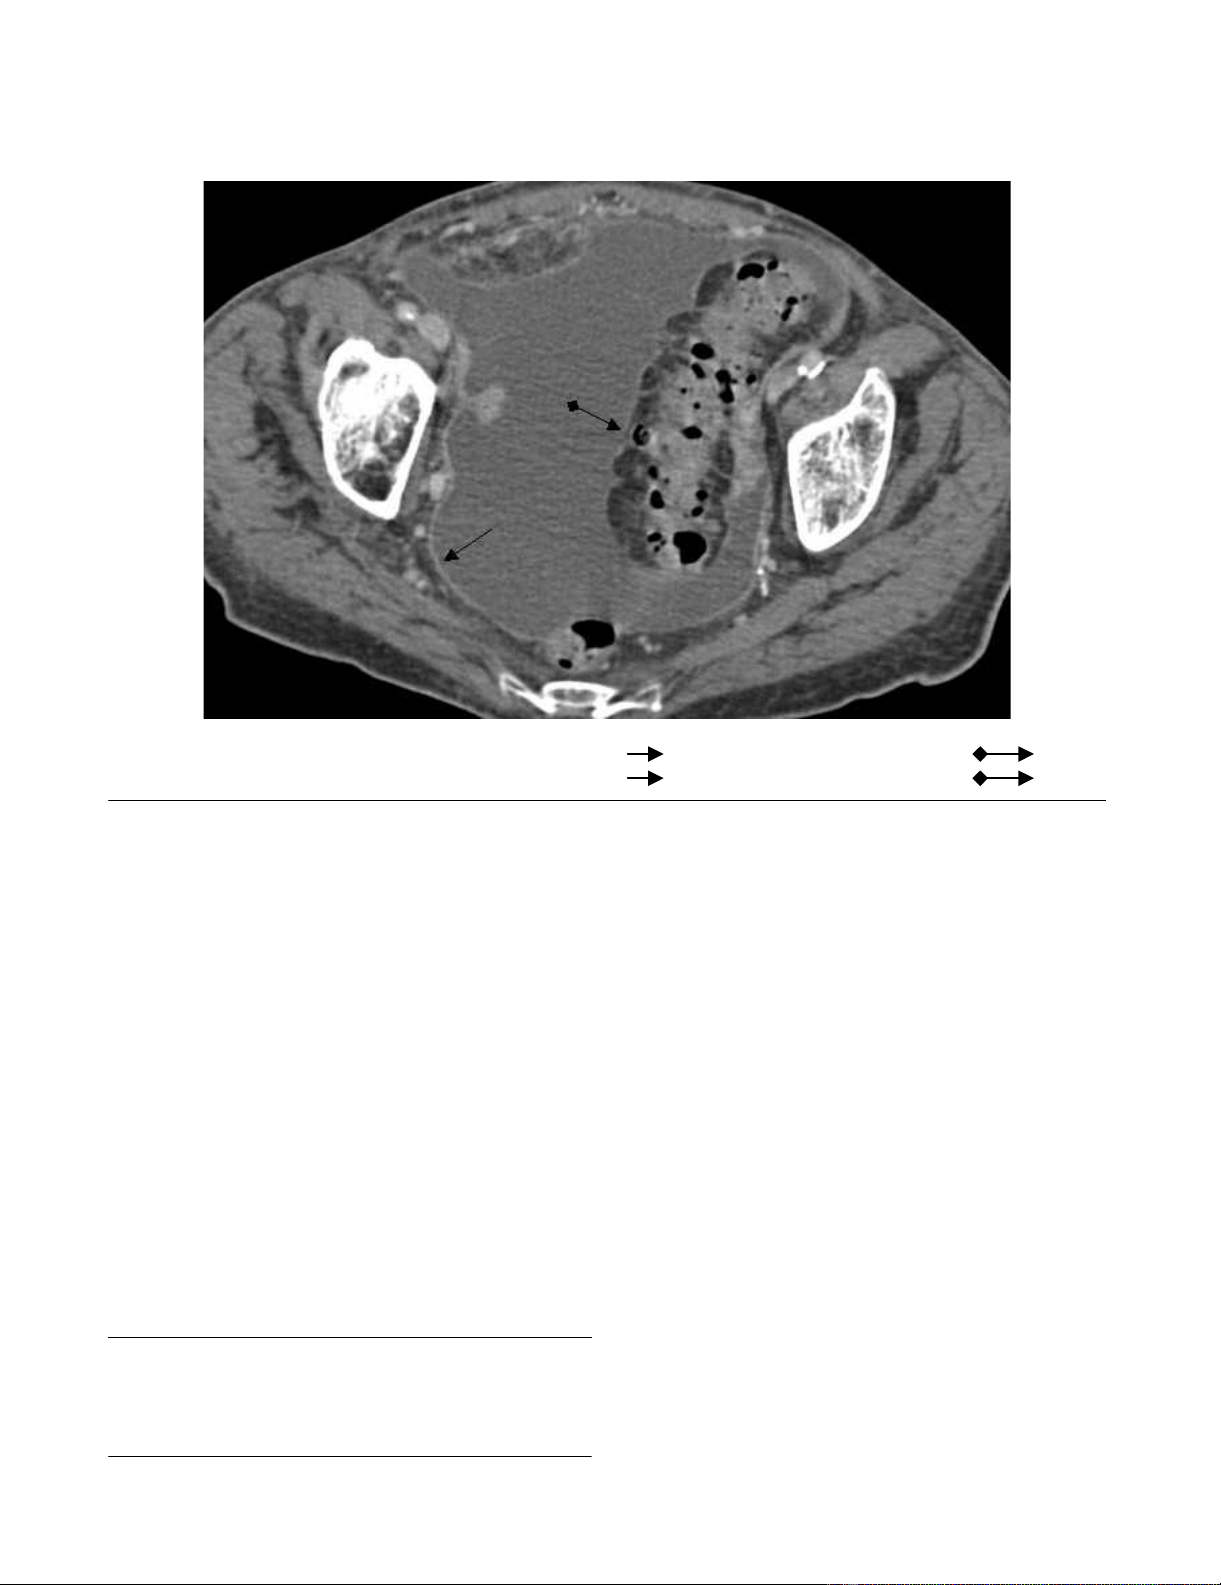

CT scan of the chest showed bilateral pleural effusions

without lymph node swellings. Abdominal ultrasonogra-

phy revealed massive ascites with multiple septa. A CT

scan of the abdomen showed a thickened intestinal wall

located in the sigmoid colon (Fig. 1) and pronounced

enhancement of the peritoneum. There were no masses or

lymph node swellings in the abdominal cavity. Esoph-

agogastroscopy and ileocoloscopy revealed no ulcer or

stenosis in the colon or ileum.

CT pelvis pronounced contrast enhancement of the peritoneum ( ); thickened wall of the sigmoid colon ( )

Figure 1

CT pelvis pronounced contrast enhancement of the peritoneum ( ); thickened wall of the sigmoid colon ( ).

In this case, massive ascites was observed with multiple

fine delicate septa on ultrasonography, and a thickened

intestinal wall located in the sigmoid colon and pro-

nounced enhancement of peritoneum was seen on CT

scan. Case reports [13] and small case studies in the liter-

ature have already reported these findings retrospectively

and prospectively [14-17].